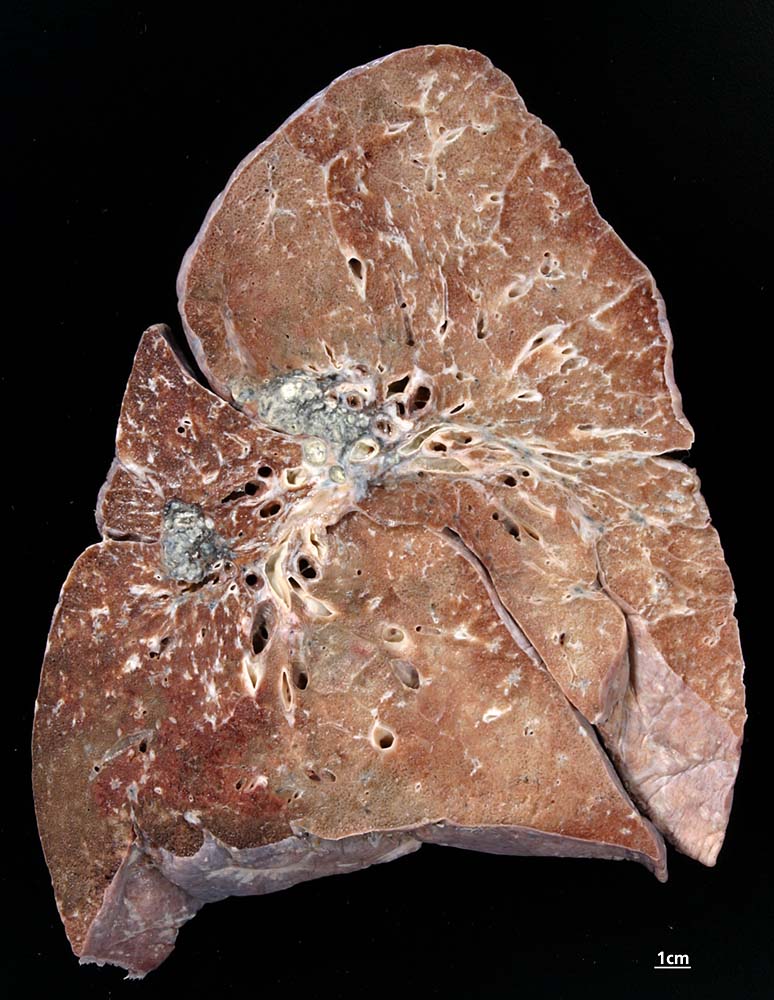

Lokalisation: Jedes Organ kann befallen werden. Besonders häufig erkranken: Lunge (95%) und mediastinale Lymphknoten (ca. 75–100%), Auge, Milz, Leber, Bronchialschleimhaut (ca. 25–50%), Haut und periphere Lymphknoten (ca. 33%), Knochen, Herz, Niere, Nervensystem und Muskulatur. Die nicht-nekrotisierenden Granulome sind oft in der Submukosa der Bronchialschleimhaut lokalisiert und können in bronchoskopisch entnommenen Biopsien nachgewiesen werden.

Morphologie: Die Morphologie der Erkrankung ist stadienabhängig. Initial findet sich eine lymphozytenreiche Alveolitis mit wenigen kleinen Granulomen. Die Granulome bestehen aus Aggregaten epitheloider Histiozyten teilweise mit Beteiligung von mehrkernigen Riesenzellen. Im Verlauf entwickeln sich zellreiche Granulome entlang der bronchovaskulären Bündel und der Interalveolarsepten, welche später konfluieren und vernarben. Die Riesenzellen können Asteroidkörperchen (sternförmige Kristalle) oder Schaumannkörperchen (lamelläre Verkalkungen) enthalten. Ein Teil der Patienten entwickelt eine irreversible Lungenfibrose.

Diagnostik: Die Krankheitsaktivität wird anhand der Klinik, des Röntgenbefundes und der Lungenfunktion bestimmt, seltener durch Bronchoalveoläre Lavage (CD4/CD8-Zellquotienten) oder Serum-ACE Wert (Angiotensin converting enzyme). Die häufigste Veränderung im Thoraxröntgenbild stellt die bihiläre und mediastinale Lymphknotenvergrösserung dar. Verschiedene Formen von Lungeninfiltraten, Fibrose und Narbenbildungen können hinzukommen. Zur Bestätigung der Diagnose ist in den meisten Fällen eine Biopsie erforderlich. Meist wird eine Bronchusbiopsie durchgeführt (in 70-80% positiv). Hiläre Lymphknoten, Haut, Konjunktiva oder Lippe können ebenfalls biopsiert werden. Biopsien aus der Leber oder Scalenuslymphknoten sind ungeeignet, da Granulome in diesen Lokalisationen sehr unspezifisch sind. Die Sarkoidose lässt sich beweisen mit einer Broncho-Alveolären Lavage (BAL) mit einer Sensitivität von >90% wenn: Lymphozytenzahl 40–60%, > 90% T-Zellen und T4/T8-Quotient > 2 (normal: 1,6).